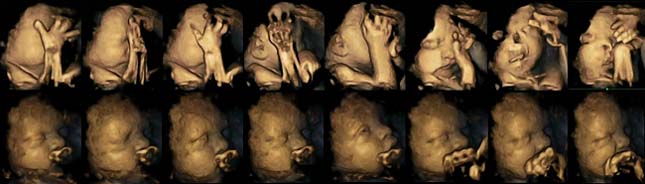

A felső sorban a dohányzó, az alsóban pedig a nem dohányzó nők kisbabáiról készült felvételek láthatóak. (Fotó: Durham University)

A Durham és a Lancaster Egyetem kutatói dohányzó és nem dohányzó anyukák kisbabáiról készítettek nagyfelbontású 4D-s ultrahangképeket a terhesség 24., 28., 32. és 36. hetében. Húsz anyukát vizsgáltak, akik közül négyen naponta átlagosan 14 szál cigarettát szívtak el. A kutatók az ultrahangos felvételeken megfigyelték a magzatok arc- és kézmozgását, és azt állapították meg, hogy a dohányzó anyák babái gyakrabban mozgatják a szájukat és sokkal többször fogják meg a fejüket, mint a nem dohányzó kismamák magzatai. A dohányos nők babáinál csak később szűntek meg a kéz- és szájmozgások, mivel azokat iránytó idegrendszer lassabban fejlődött ki. Ez azt jelenti, hogy a dohányzás lassítja a babák idegrendszeri fejlődését.